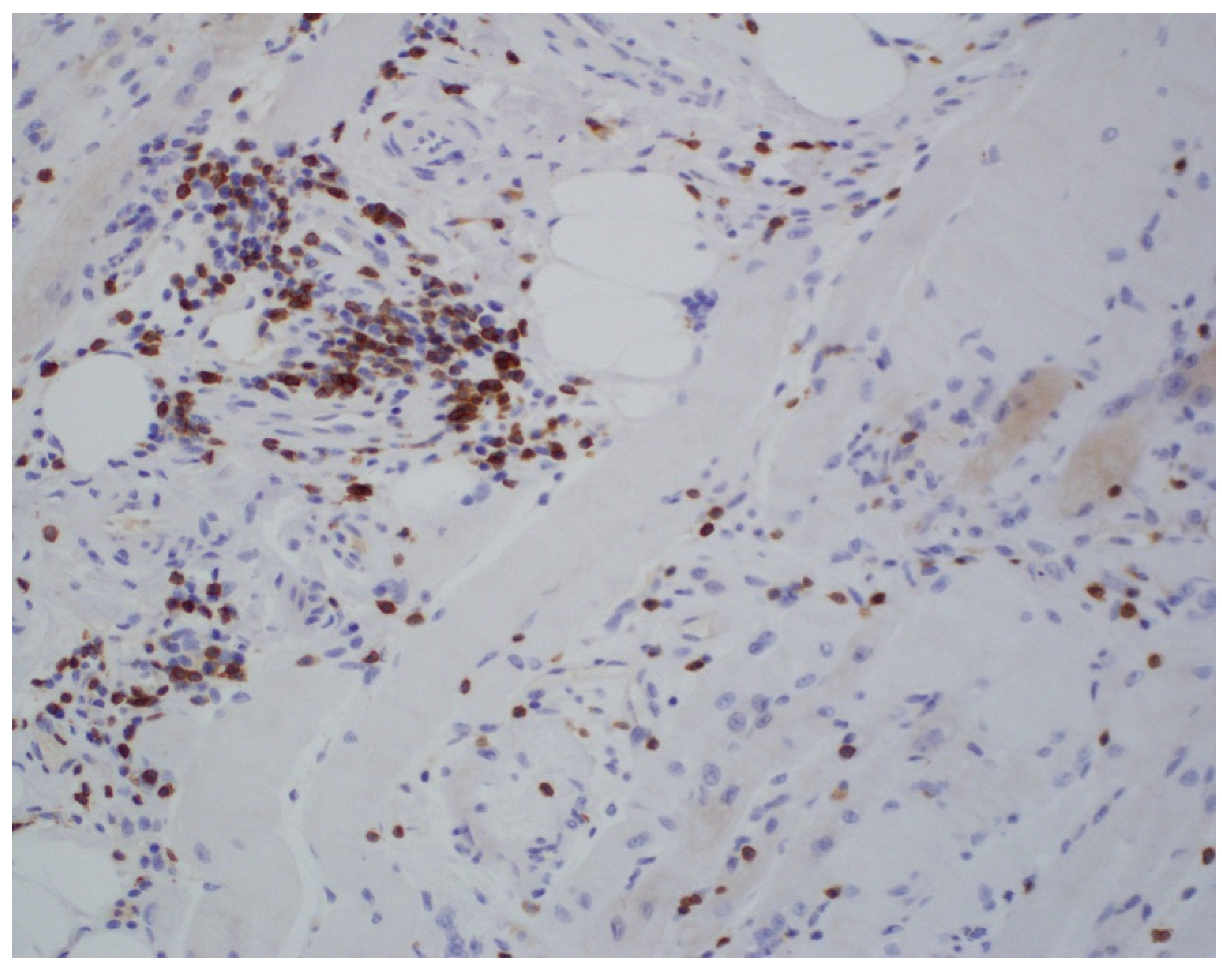

Figure 1.

Hematoxylin and eosin stain: segmental necrosis and inflammatory infiltrate without vessel wall destruction.